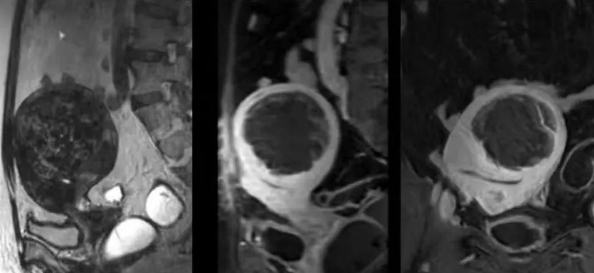

陳寶瑩主任首先給祝女士進行了詳細的盆腔磁共振評估,發(fā)現(xiàn)子宮肌瘤比較大,直徑七公分,類型和位置都適合做磁波刀治療。陳寶瑩主任立即為她制定了個性化治療方案,并為她完成幾項術前檢查。

治療當天,為緩解祝女士的緊張心情,陳寶瑩主任和她進行了充分溝通。術前準備就緒后,治療正式開始了。治療過程中,患者全程清醒,可以及時反饋治療感受。醫(yī)生也即時調整,確保整個治療安全有效,兩小時后治療順利結束,患者體驗度好。即時評估發(fā)現(xiàn)7公分的子宮肌瘤被消融掉80%,達到了預期目標。祝女士觀察一個小時后,沒有什么不舒服即回家了。